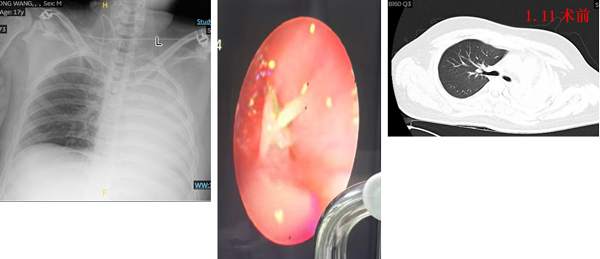

患者是一名17岁少年,车祸外伤后出现左肺完全性不张,胸闷、呼吸困难症状进行性加重。经胸部检查,发现患者左主支气管远端离断,同时存在左腿骨折,急需肺部病情改善后进行骨折手术。传统治疗方案需进行开胸支气管重建手术,但这一方案创伤巨大、恢复缓慢,且手术风险高,存在左全肺切除的可能,将对患者未来生活质量造成长期影响。面对危急复杂的病情,呼吸与危重症医学科科室负责人刘毅教授主持启动多学科会诊,经过充分论证,决定采用创伤更小的介入治疗方案。呼吸与危重症医学科副主任医师王永刚主刀,在胸外科病区副主任、副主任医师王光辉,胸外科副主任医师马国元协调保障下,实施球囊扩张联合硬质支气管镜下硅酮支架置入术。

在麻醉与围术期医学科团队协助下,王永刚首先通过硬质支气管镜建立稳定的气道通路,清晰暴露断裂闭塞的左主支气管。随后对狭窄闭塞段应用导丝及活检钳探测远端气道,并实施球囊扩张,逐步打通梗阻的气道通道。最后精准置入硅酮支架,为断裂的支气管提供支撑,重建气道通畅性。整个手术过程团队配合默契,短时间内完成操作。术后患者胸闷、呼吸困难症状即刻缓解,复查胸片显示左肺复张良好,各项生命体征平稳。目前,患者已顺利完成骨折手术出院。

术前

术后